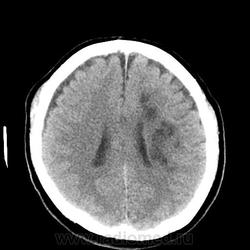

Пациент поступил 5.05.14 с жалобами на головную боль, головокружение, слабость в правой руке и ноге. Выполнена КТ головного мозга, данных за наличие ОНМК не обнаружил, только 2 постишемические кисты, в анамнезе инсульт в феврале 2014г. 18.05.14 повторно КТ в связи с нарастающей неврологической симптоматикой правостороннего гемипареза. В базальных ганглиях и лобно-теменной области слева выявлено наличие гиподенсных очагов, сливающихся в фокусы. Ишемический инсульт? Сначала иссл-ие за 18.05, затем за 5.05. Еще смущает увеличенный размер гипофиза. Буду рад любым комментариям. Просьба сильно не ругаться, это моя первая публикация.

Теперь иссл-ие на момент поступления 05.05.14